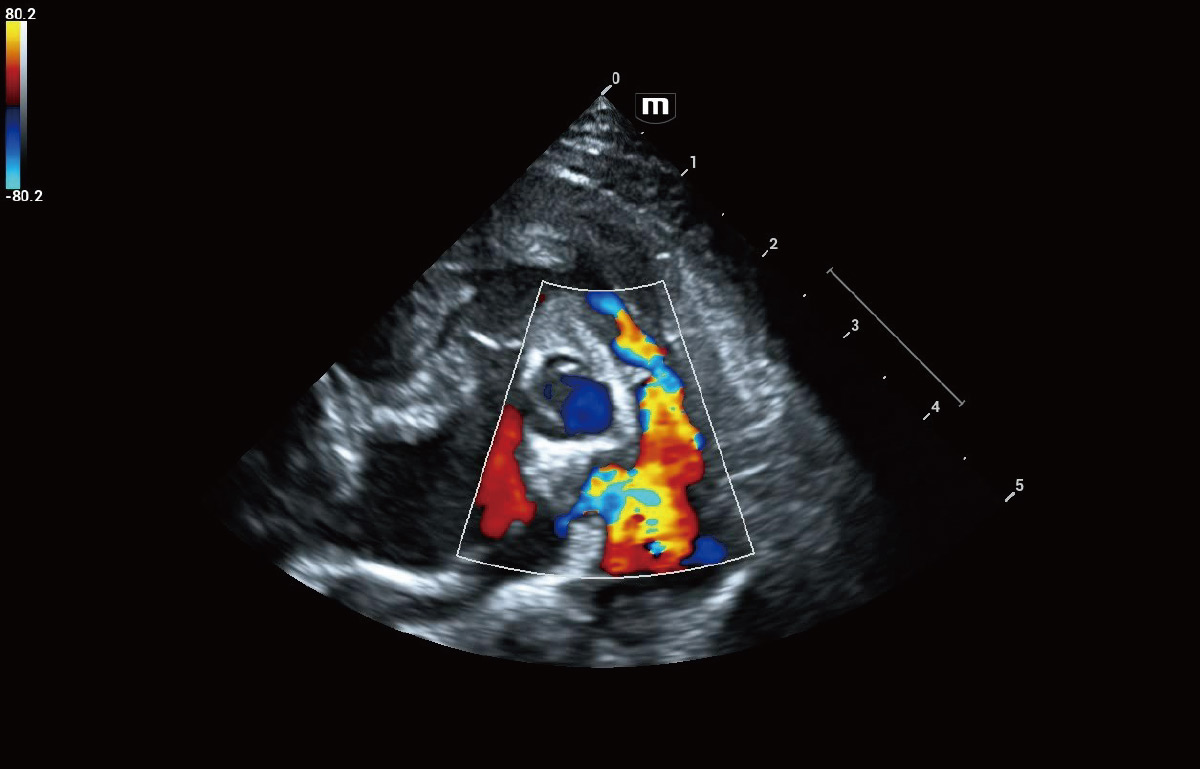

Cardiology Solution